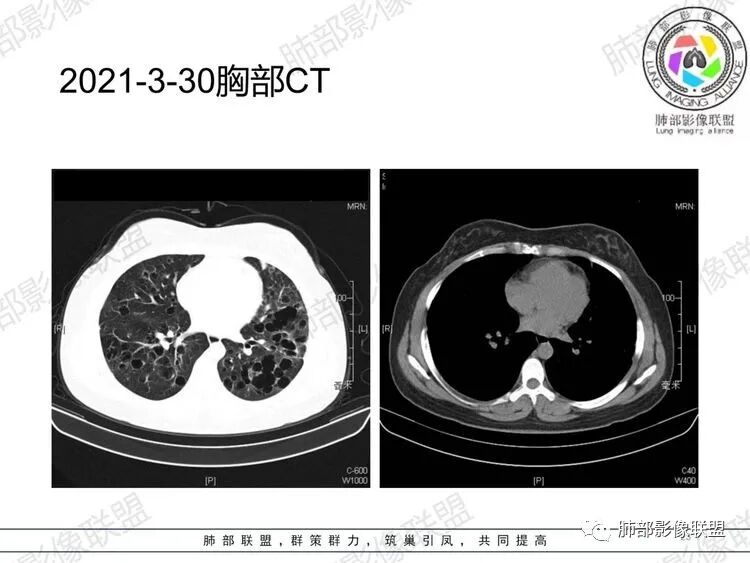

晨读:女,31,间断咳嗽、咳痰9月。卵巢交界性囊腺瘤术后。胸部CT:双肺多发大小不等薄壁囊腔影,部分融合,形态不规则,个别囊壁偏厚。右肺上叶及左肺下叶纤维索条影。左下叶不规则囊腔影,壁不均匀增厚,周围不规则实性成分加GGO,放射性毛刺,胸膜牵拉。考虑:囊腔型Ca?转移?鉴别PLCH,Lam,LIp,BHD,CF,CPAM等,听大咖解析。

家族史(—),3年前有右侧附件交界性浆粘性囊腺瘤手术史。支气管镜检查病理:慢性炎,部分肺泡内见吞噬细胞。CA199升高。自身抗体阴性。

胸部CT:两肺多发囊腔,中上肺受累为主,囊腔形态不规则(囊有点丑),分叶状,囊壁厚薄不均,大部分囊壁薄。尚有一些结节影。

5.囊腔型肺转移瘤:常见于头颈部的鳞状上皮癌、胃肠道的腺癌、女性生殖系统肿瘤、肺外肉瘤的转移。

晨读病例有妇科肿瘤手术史,肺内病变转移瘤可能性大(而且一般盆腔肿瘤手术前基本都会完善胸部X检查,能够顺利完成手术估计手术时肺内无明显病灶),但肺囊肿有较明显的融合,这在转移瘤中较少见。综合上述考虑囊腔型肺转移瘤,鉴别PLCH。

病理结果:肺粘液腺癌(转移不除外)

盆腔肿瘤病理复检结果为:交界性粘液性肿瘤